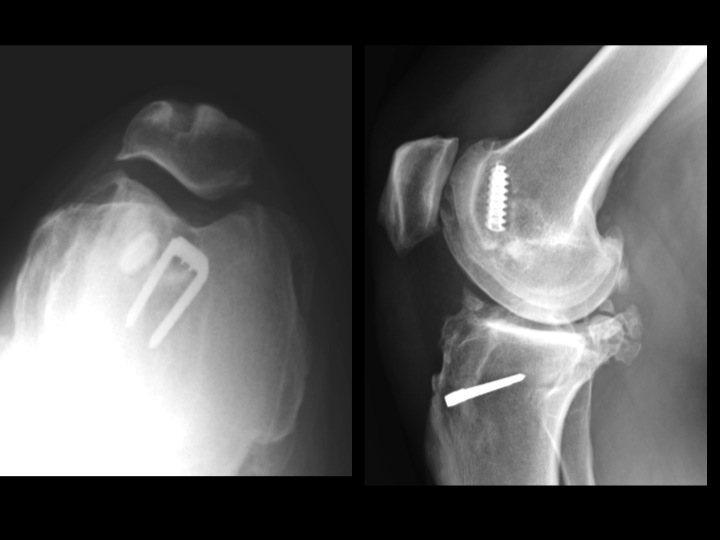

44 yr old female knee pain, previous ACL graft

The tunnel placement seems deceptively normal in the AP view. Check out the anterior location of the femoral tunnel in the lateral and skyline views. Is this crazy? Is there any circumstance in which this is acceptable? Severe medial OA suggests that it is not OK.

ACL graft device ( RID5523 )